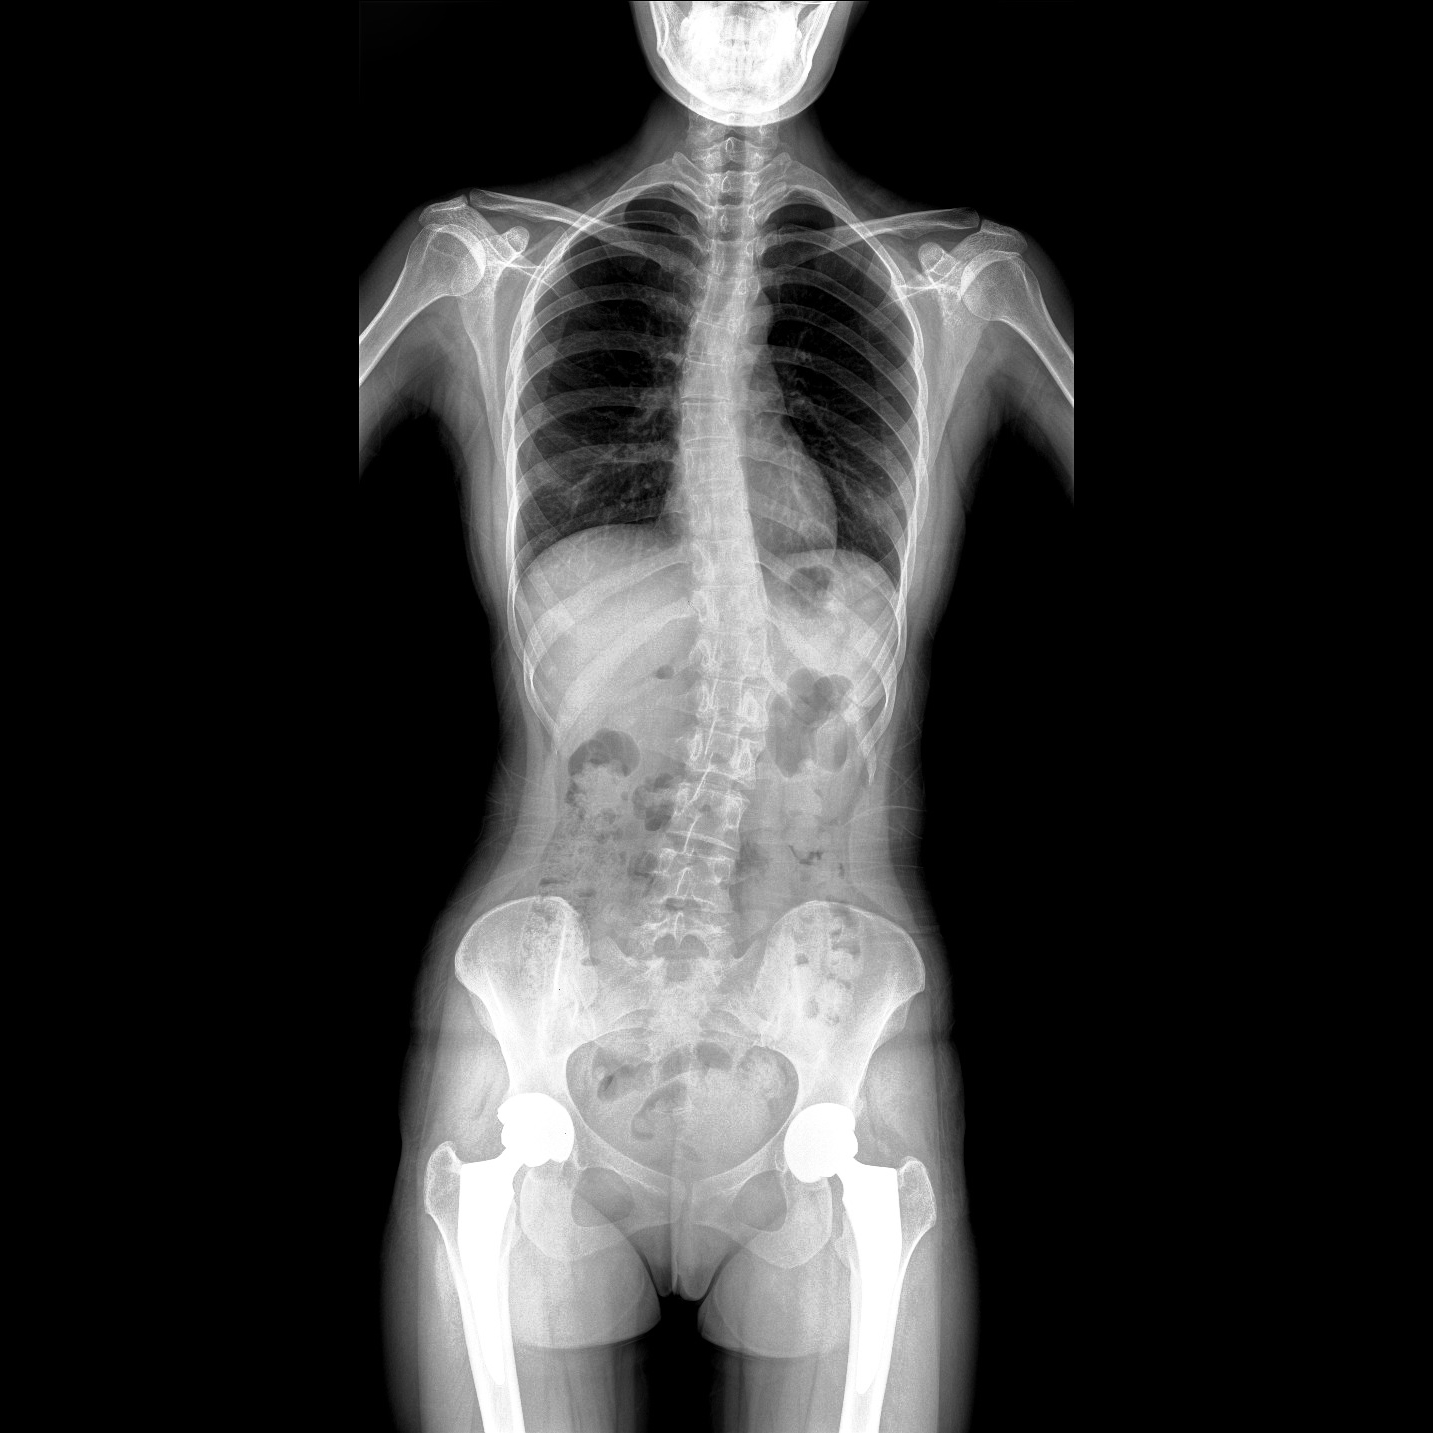

17"*34"有效視野,一次成像不拼接。相較于多張攝影再軟件拼接的DR設(shè)備,PLX8600解決了拼接圖像存在密度不均勻,拼接處圖像配準(zhǔn)和放大效應(yīng)等問(wèn)題,給臨床帶來(lái)了大視野影像解決方案,可一次性覆蓋全脊柱或雙下肢影像。

支持全脊柱攝影、雙下肢攝影、脊髓造影、復(fù)雜創(chuàng)傷、人工關(guān)節(jié)置換、關(guān)節(jié)損傷的修復(fù)重建等大視野臨床應(yīng)用